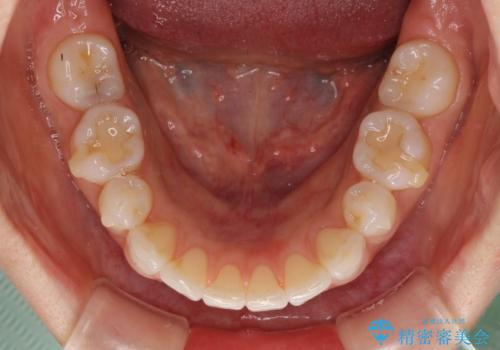

矯正治療の後戻り インビザラインによる再矯正治療

- 以前ワイヤー装置にて行った抜歯矯正の後戻りを気にして来院された患者様です。

前歯のデコボコにより、やや口元が突出した印象となっていたため、口元も引っ込めることとしました。

上下顎前歯に積極的にIPR(歯と歯の間を削る)を行い、インビザラインを用いて治療していくこととしました。

デコボコが解消されるのはもちろんのこと、突出感のあった前歯を引っ込めることができ、患者様には大変満足していただきました。